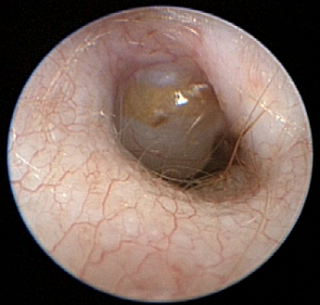

Diagnosis may be conducted using a variety of modalities. In cavaliers in particular, if the case is severe enough that the pars flaccida, the top portion of the dog's tympanic membrane (eardrum), is bulging, the condition may be visible on x-rays and even diagnosed manually with an otoscope (right). However, in cases in which the dog is in pain, or there are large amounts of wax or the dog does not tolerate the examination, PSOM cannot be excluded or confirmed solely by otoscopy.

A more sophisticated form of otoscopy is video-otoscopy. It uses a

high-powered, fiber-optic camera which enables in-depth views of the two

sections of the canal -- vertical and horizontal -- and the eardrum.

General anesthesia is required for this procedure. It is combined with a

port that enables flushing and suction of the

canal,

to remove wax, mucous, and debris. This is necessary to thoroughly clean

the canal for best visualization of the eardrum.

canal,

to remove wax, mucous, and debris. This is necessary to thoroughly clean

the canal for best visualization of the eardrum.

In this video-otoscopic image at the left, of the left ear canal and tympanic membrane of a cavalier, the red arrow points to a large, bulging pars flaccida. (Photo from Dr. Lynette Cole's December 2015 report.) However, cavaliers may have PSOM even though their pars flaccida is flat rather than bulging.

Video-otoscopy also is used in preparation of and during the surgical procedure, myringotomy, described below.